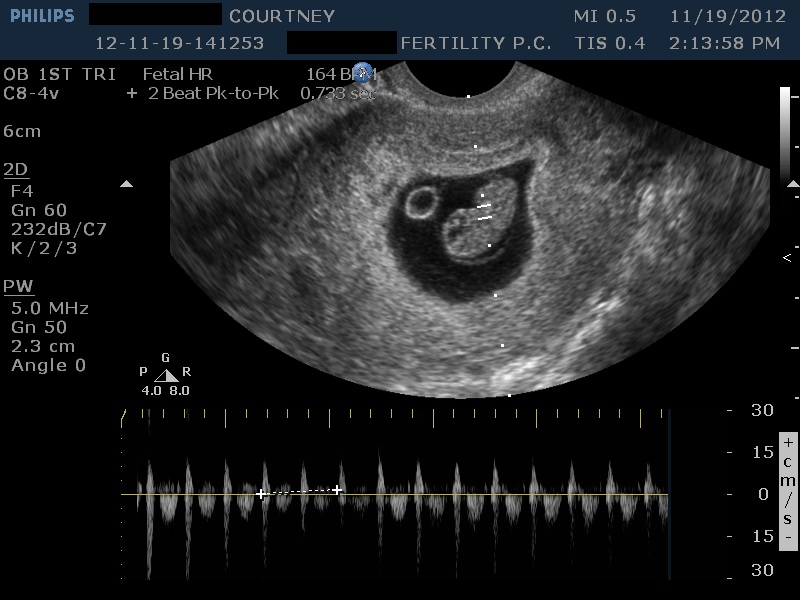

12-11-19-141253_DONALDSON_20121119_141253_0000 November 19, 2012 by Courtney Leave a comment ← Previous Image Next Image → 8w1d – Heartbeat of 164 bpm Like Loading...